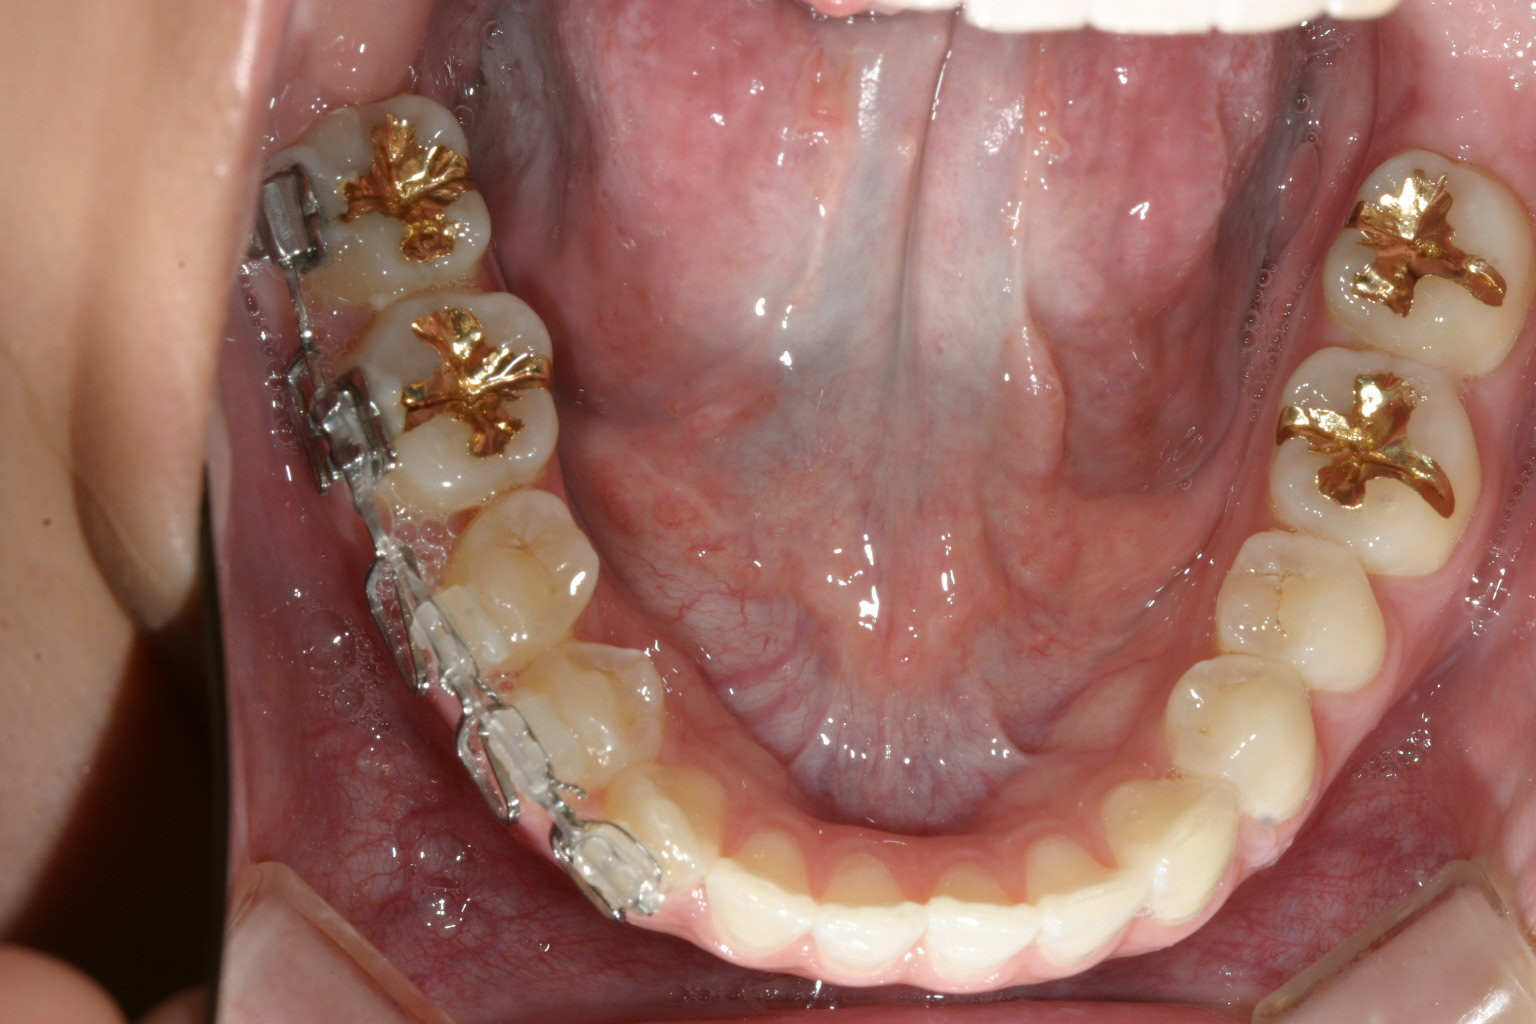

下顎は一見綺麗に見えるのですが右の奥から3本目を見てください。 歯が90°回転しているのが見受けられます。 こういった歯をインビザライン単独で治療するにはかなり難易度が高く治療に相当の期間がかかり 結果として上手く戻らない事が多いです。 その為今回は部分ワイヤーを併用しました。

インプラントとワイヤーとバネの力を利用して右側臼歯を遠心移動してるのが分ります。

マルチループワイヤーを用いて右奥から3番目の小臼歯が上手く回転し終わりました。

上にインプラントとワイヤーとバネです。 下はマルチループです。

回転途中の写真です。